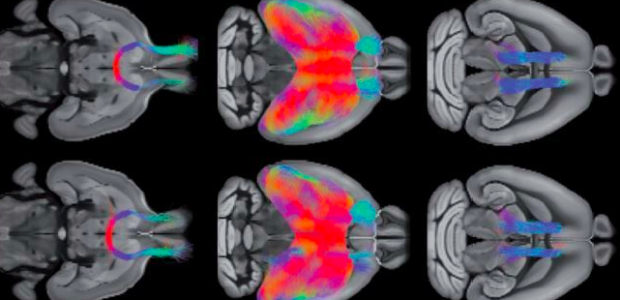

In una prima fase di ricerca il team di scienziati ha misurato la funzione cerebrale di 30 bambini con disturbi dello spettro autistico, analizzando le scansioni cerebrali in 3D dei piccoli pazienti ottenute tramite risonanza magnetica funzionale. I bambini, già coinvolti in uno studio statunitense, sono tutti portatori della stessa mutazione genetica nota come delezione 16p11.2. Lo studio ha permesso ai ricercatori di identificare alterazioni cruciali presenti all’interno della corteccia prefrontale dei bambini, tali da impedire all’area di interagire in modo efficace con il resto del cervello generando sintomi tipici dell’autismo quali il ridotto interesse a instaurare relazioni sociali e problemi nella comunicazione.

In una seconda fase, continua Gozzi, “i ricercatori hanno traslato la ricerca su organismi modello – in questo caso, i topi – nei quali è stata riprodotta la mutazione 16p11.2”. Dopo aver individuato, sempre tramite tecniche di neuroimaging, gli stessi deficit della corteccia prefrontale presenti nei bambini, gli scienziati hanno potuto esaminare le connessioni neuronali dei topi a livello neuroanatomico fine, per cercare di individuare anomalie strutturali potenzialmente all’origine dei difetti di connettività cerebrale, riconducibili allo specifico disturbo dello spettro autistico riscontrato nei bambini portatori della delezione 16p11.2.